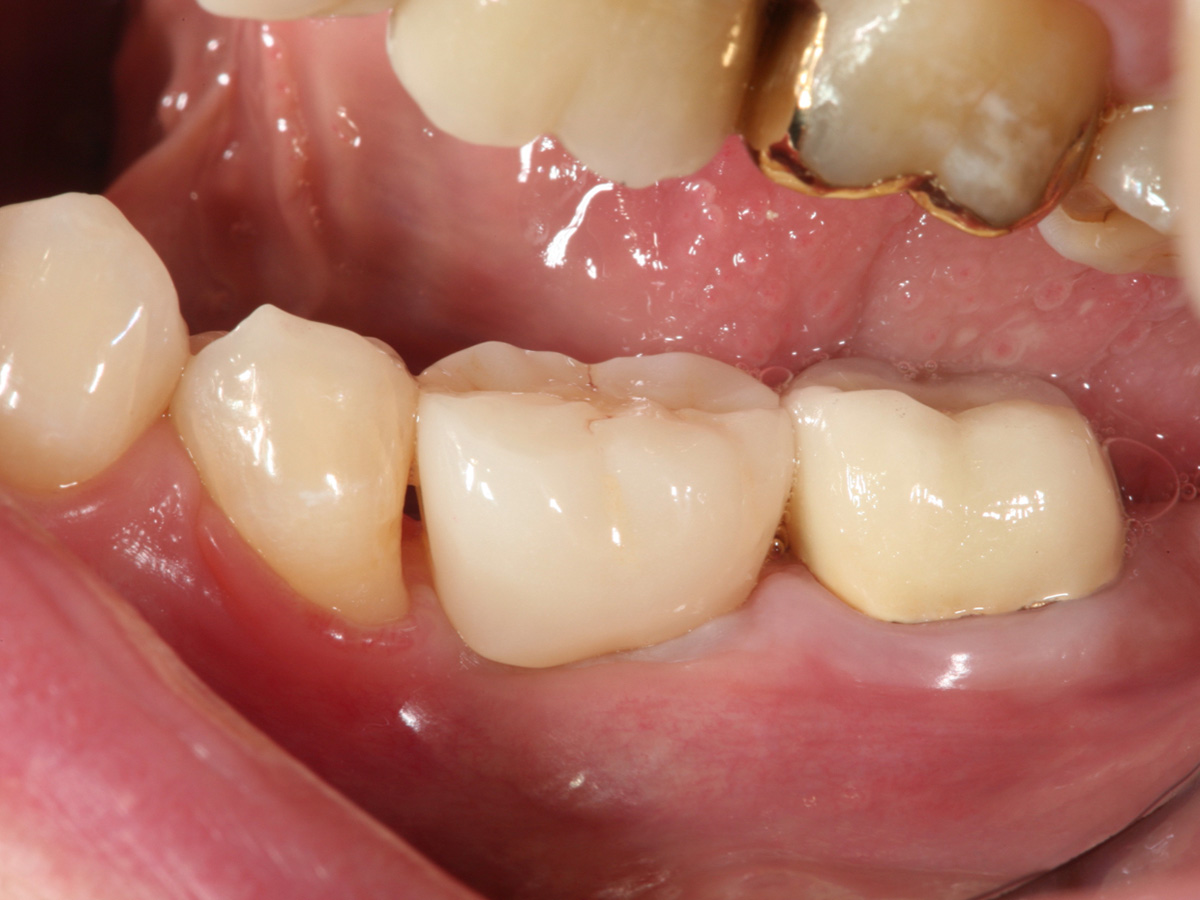

Bei den Abb. 10 und 11 handelt es sich um das Einzelzahnröntgen der Situation und das klinische Bild der implantatgetragenen Versorgung.

Abbildung 11

Endergebnis: Die implantatgetragene Versorgung.